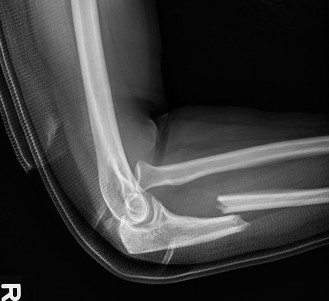

A 36-year-old, right-hand-dominant male presents to the emergency department with right arm and elbow pain af…